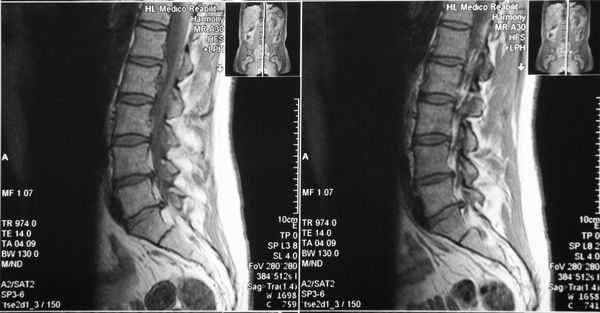

При этом, рентгенографические исследования (МРТ, КТ, УЗИ) стопных отделов под нагрузкой, позволяют выявить наличие/отсутствие различных деформационных изменений, остеофитов, переломов, а также иных видов проблем, провоцирующих изменение нормальной формы канала предплюсны.

Как правило, рентген помогает специалисту получить оптимально корректную информацию и, на ее основе, применить наиболее эффективную тактику лечения - консервативную, либо хирургическую.

Рис 3. МР-признаки наличия жидкостного ганглия, оказывающего патологическое давление на большеберцовый нерв.